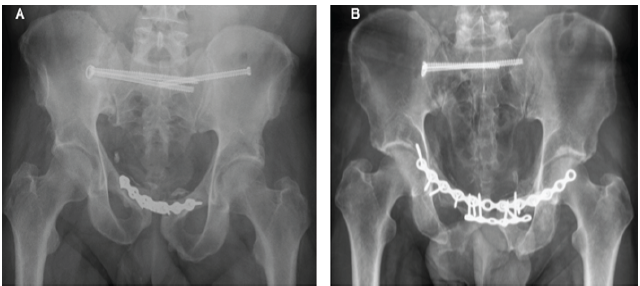

Pelvic stabilization proceeded with anterior reconstruction plating and percutaneous iliosacral screws (Fig. 4). No intraoperative complications occurred. One patient developed a superficial wound infection requiring debridement. Hospital stay was 9 and 12 days, respectively. At 3- and 6-month follow-up, both patients showed complete radiological union and preserved testicular volume without pain or atrophy.

Figure 4: Postoperative pelvic radiographs. (a) Case 1: anteroposterior view showing fixation with a symphyseal plate and bilateral iliosacral screws. (b) Case 2: anteroposterior view after fixation with double anterior plating and right-sided iliosacral screws.